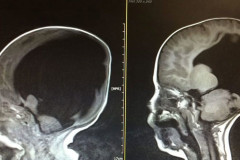

ԲԱՑԱՌԻԿ. Աշխարհում առաջին մարդը, ով 40 տարի ապրել է առանց ուղեղի. Ահա, թե ինչպես